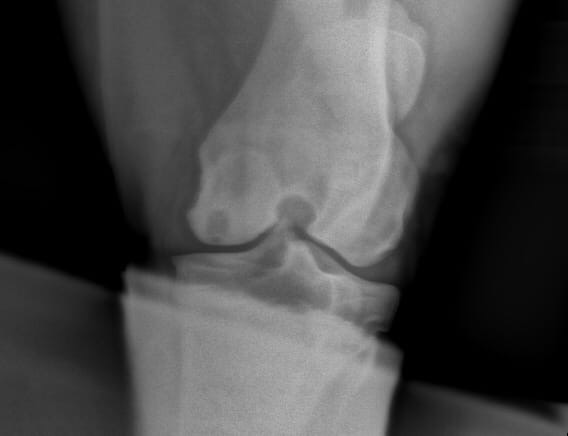

В нашем случае обнаружилась киста в коленом суставе. Конь резко захромал и потом его так же резко "отпускало". Так же и сейчас, то хромает, то не хромает. Хотя носится в леваде как сумасшедший. Сустав не опухший внешне изменений не видно. Почти все рекомендуют лошадь продавать, так как лечение препаратами якобы результата не даст и нужна артроскопия. Я бы ее и сделала, но в нашем регионе это невозможно. Везти в Москву + операция выйдет под 300 тысяч. Не целесообразно совершенно.